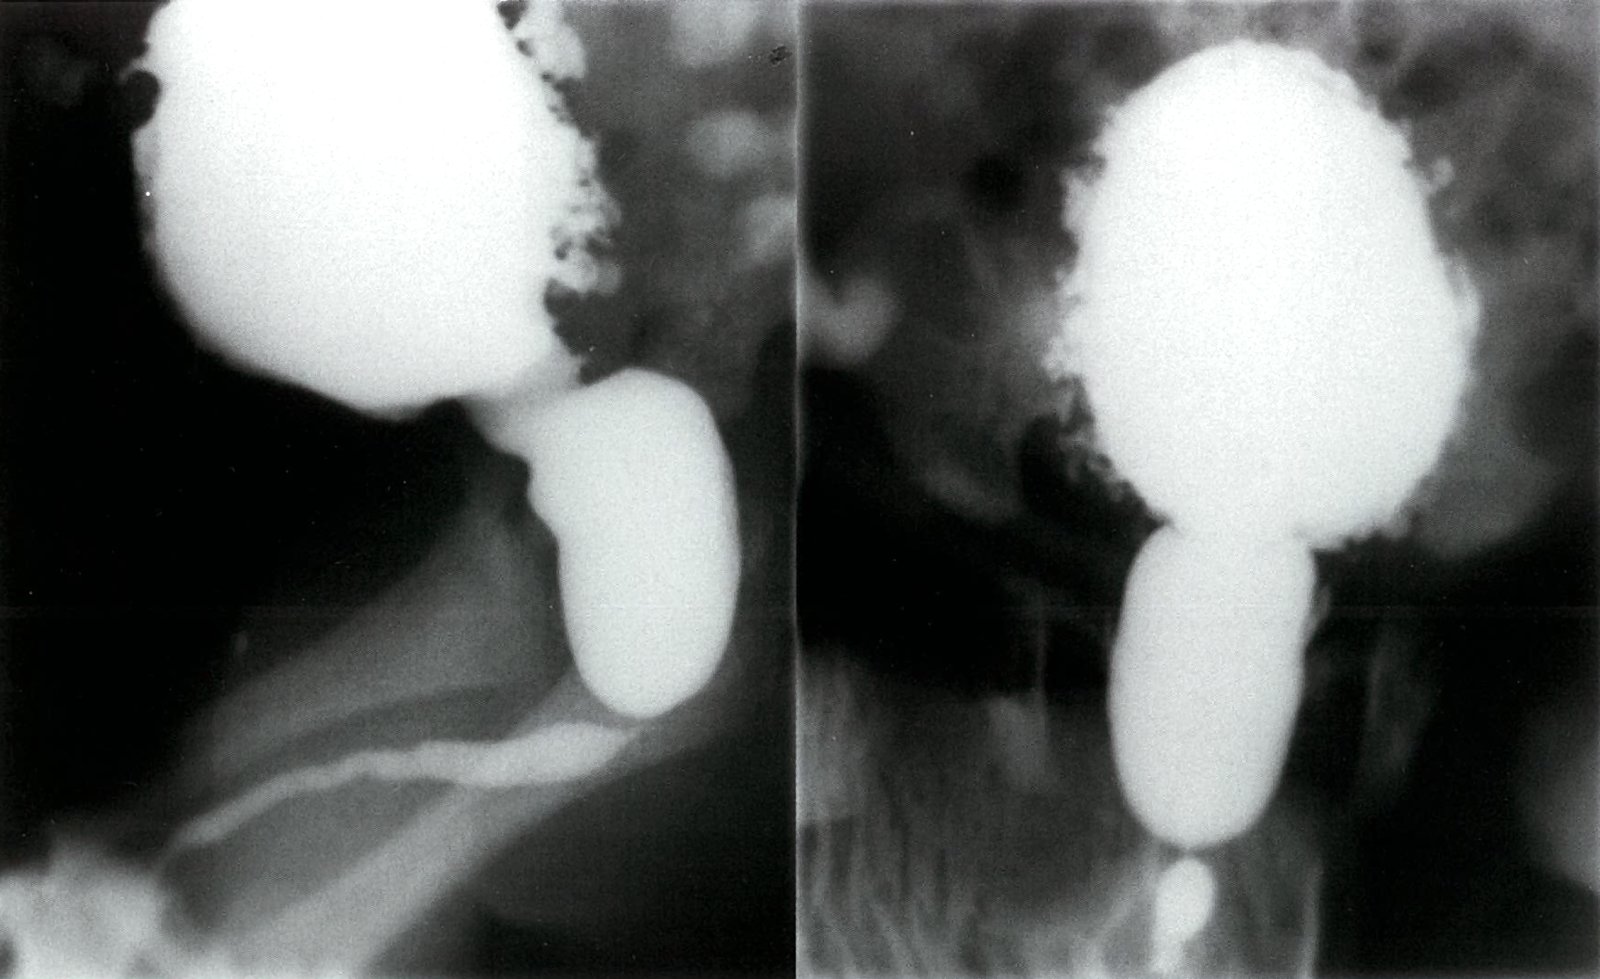

Voiding cystourethrography [2][5][14]

• Only used if there is high suspicion for VUR because of its invasive nature and use of radiation

• Potential findings include:

• Visualization of VUR (see ā€œDiagnostics of VURā€) [2][3]

• Obstructive uropathy (e.g., stenosis, hydronephrosis)